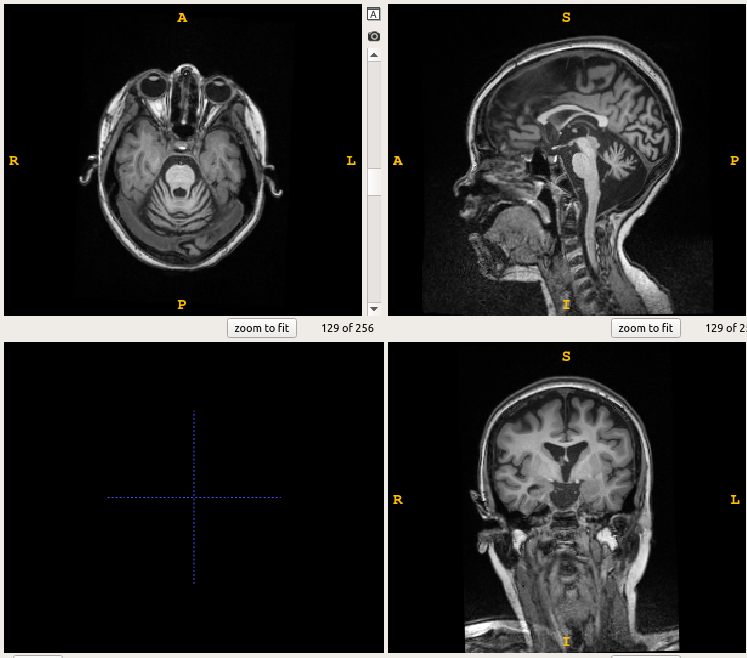

我试图翻转图片1中显示的图像,以匹配图像2的方向,但我不确定如何。

这就是如何以形象为导向: